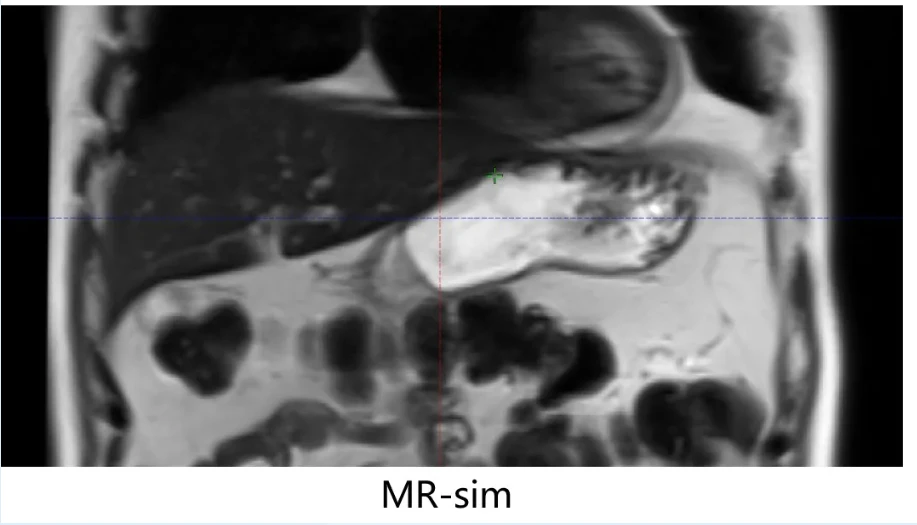

在图像配准阶段增加审核节点,在靶区勾画前,对患者所有图像的质量再次进行审核,包括伪影、定位姿势、肌肉重复性等。同时对潜在的运动影响因素进行评估,给出适当的PTV外扩边界及相应的摆位注意事项。以治疗前在线提示的方式,对后端加速器进行信息推送。若在图像配准阶段发现位置难以重复,及时给出再次定位的建议。

另外,增添了加速器复位审核制度。此节点需对上游所有信息进行汇总,并对初次摆位进行评估,适当对后续治疗提出合理的摆位建议。在配准审核中,将靶区影像与ITV结构的一致性做为检验胃肠道运动管理成功与否的关键指标。通过骨性自动配准及软组织两次配准的步骤,对摆位误差进行分析,判断是否对患者进行其他运动管理的必要。